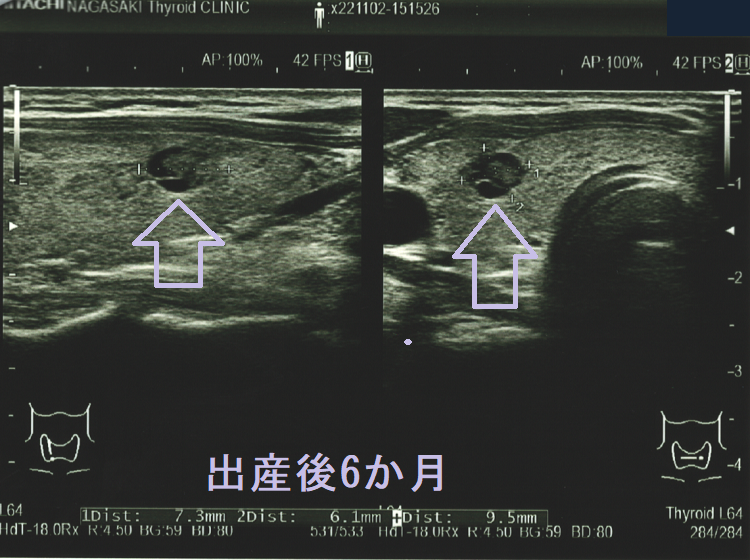

隈病院の統計では妊娠中、甲状腺微小乳頭癌の44.4%がサイズが増大するとのことです[Thyroid. 2014 May;24(5):840-4.]。もちろん、甲状腺刺激作用を持つhCGの影響が大きいと思われます[J Clin Endocrinol Metab. 1991 Oct;73(4):824-31.]が、あまり気持ちの良いものではありません。

隈病院の報告によると、50人の甲状腺微小乳頭癌妊婦のうち、

- 8%が3 mm以上の増大

- その半分が分娩後に手術

- もう半分は分娩後に甲状腺微小乳頭癌の増大が止まったため、積極的非手術経過観察(アクティブ サーベイランス)を再開

になったそうです[Thyroid. 2016 Jan;26(1):156-60.]。

妊娠前の甲状腺超音波(エコー)検査ではなかったのに、出産後に甲状腺微小乳頭癌が見つかるケースがあります。甲状腺刺激作用を持つhCG[J Clin Endocrinol Metab. 1991 Oct;73(4):824-31.][Obstet Gynecol. 1990 May;75(5):775-8.]が、隠れていた甲状腺乳頭癌細胞の増殖を促進した可能性が考えられます。